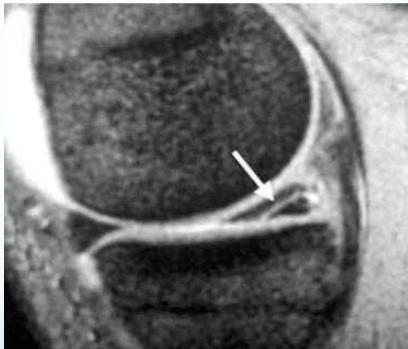

Diagnostic Studies

MRI

- Peripheral tears: Operative repair possible (due to blood supply)

Meniscal Repair

- Indications: Peripheral, longitudinal tears in red zone (due to blood supply)